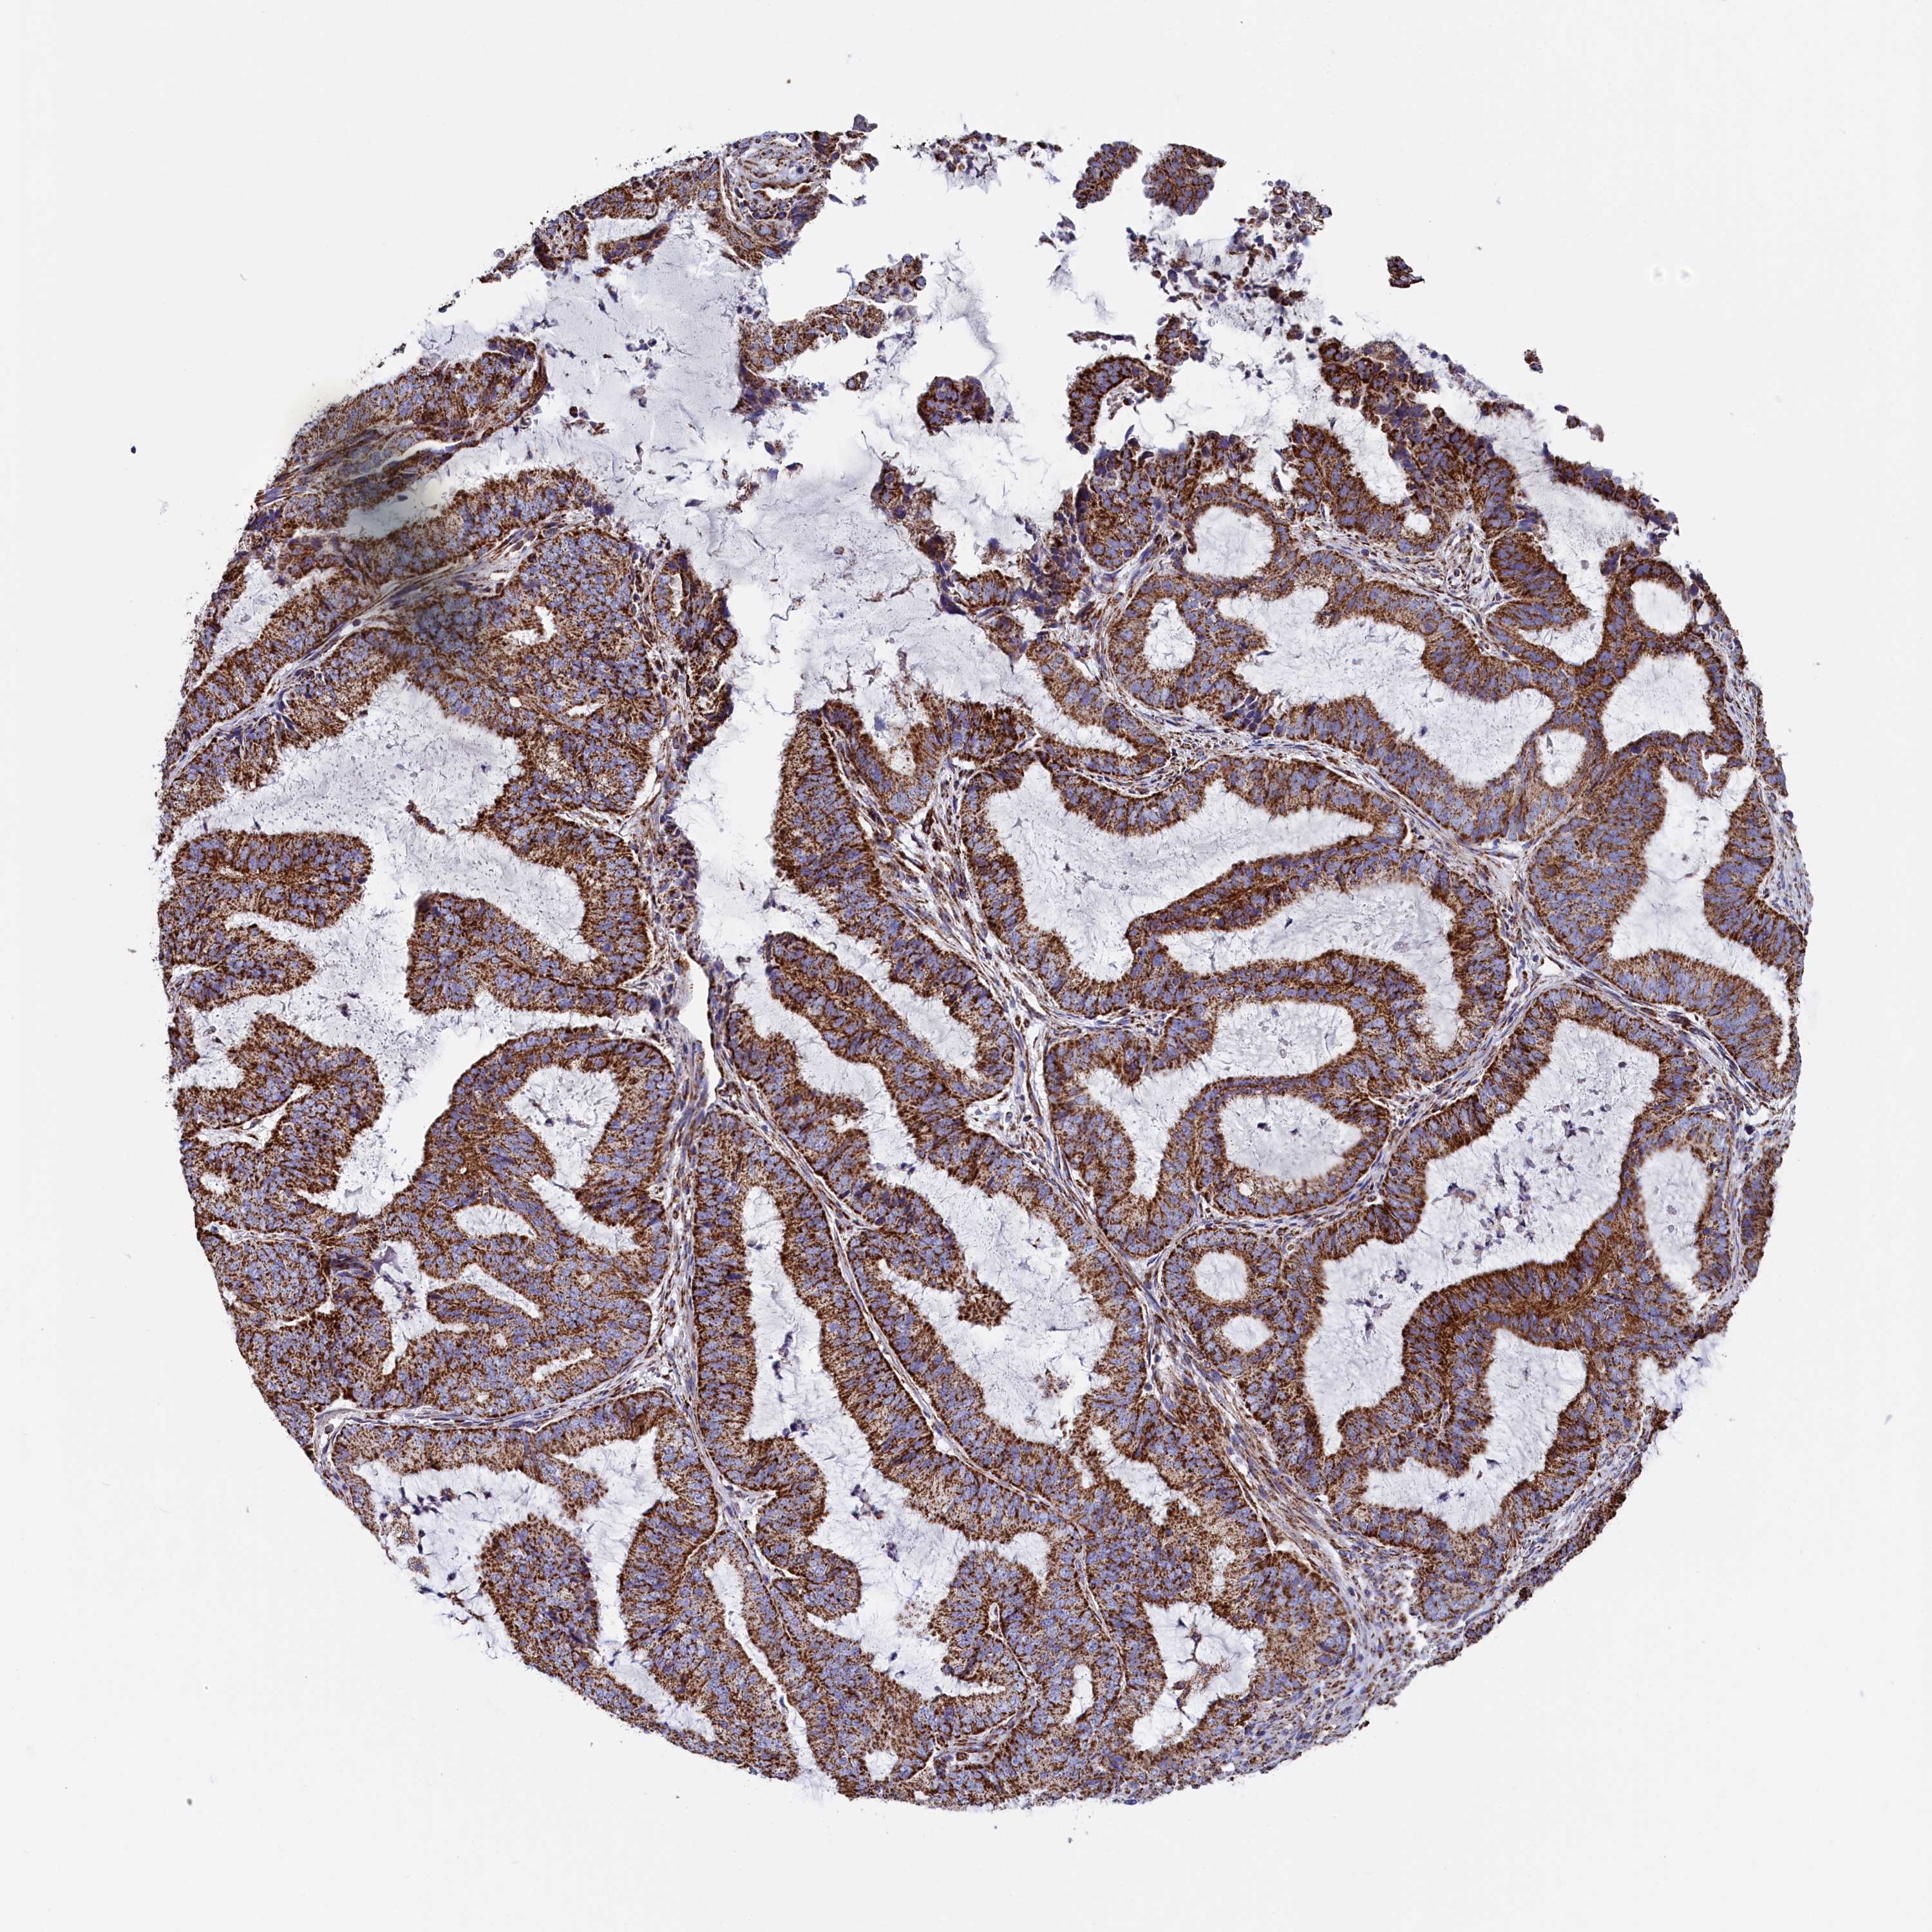

ENDOMETRIAL CANCER - Protein expressioni

A mouse-over function shows sample information and annotation data. Click on an image to view it in a full screen mode. Samples can be filtered based on level of antibody staining by selecting one or several of the following categories: high, medium, low and not detected. The assay and annotation is described here.

Note that samples used for immunohistochemistry by the Human Protein Atlas do not correspond to samples in the TCGA dataset.

Antibody stainingi

Antibody staining in the annotated cell types in the current human tissue is reported as not detected, low, medium, or high, based on conventional immunohistochemistry profiling in selected tissues. This score is based on the combination of the staining intensity and fraction of stained cells.

Each image is clickable and will lead to virtual microscopy that enables deeper exploration of all samples and also displays staining intensity scores, fraction scores and subcellular localization as well as patient and tissue information for each sample.

Antibody HPA042139

Antibody HPA058526

Staining

High

Medium

Low

Not detected

Intensity

Strong

Moderate

Weak

Negative

Quantity

>75%

75%-25%

<25%

None

Location

Nuclear

Cytoplasmic/membranous

Cytoplasmic/membranous,nuclear

Adenocarcinoma, NOS

Carcinoma, NOS